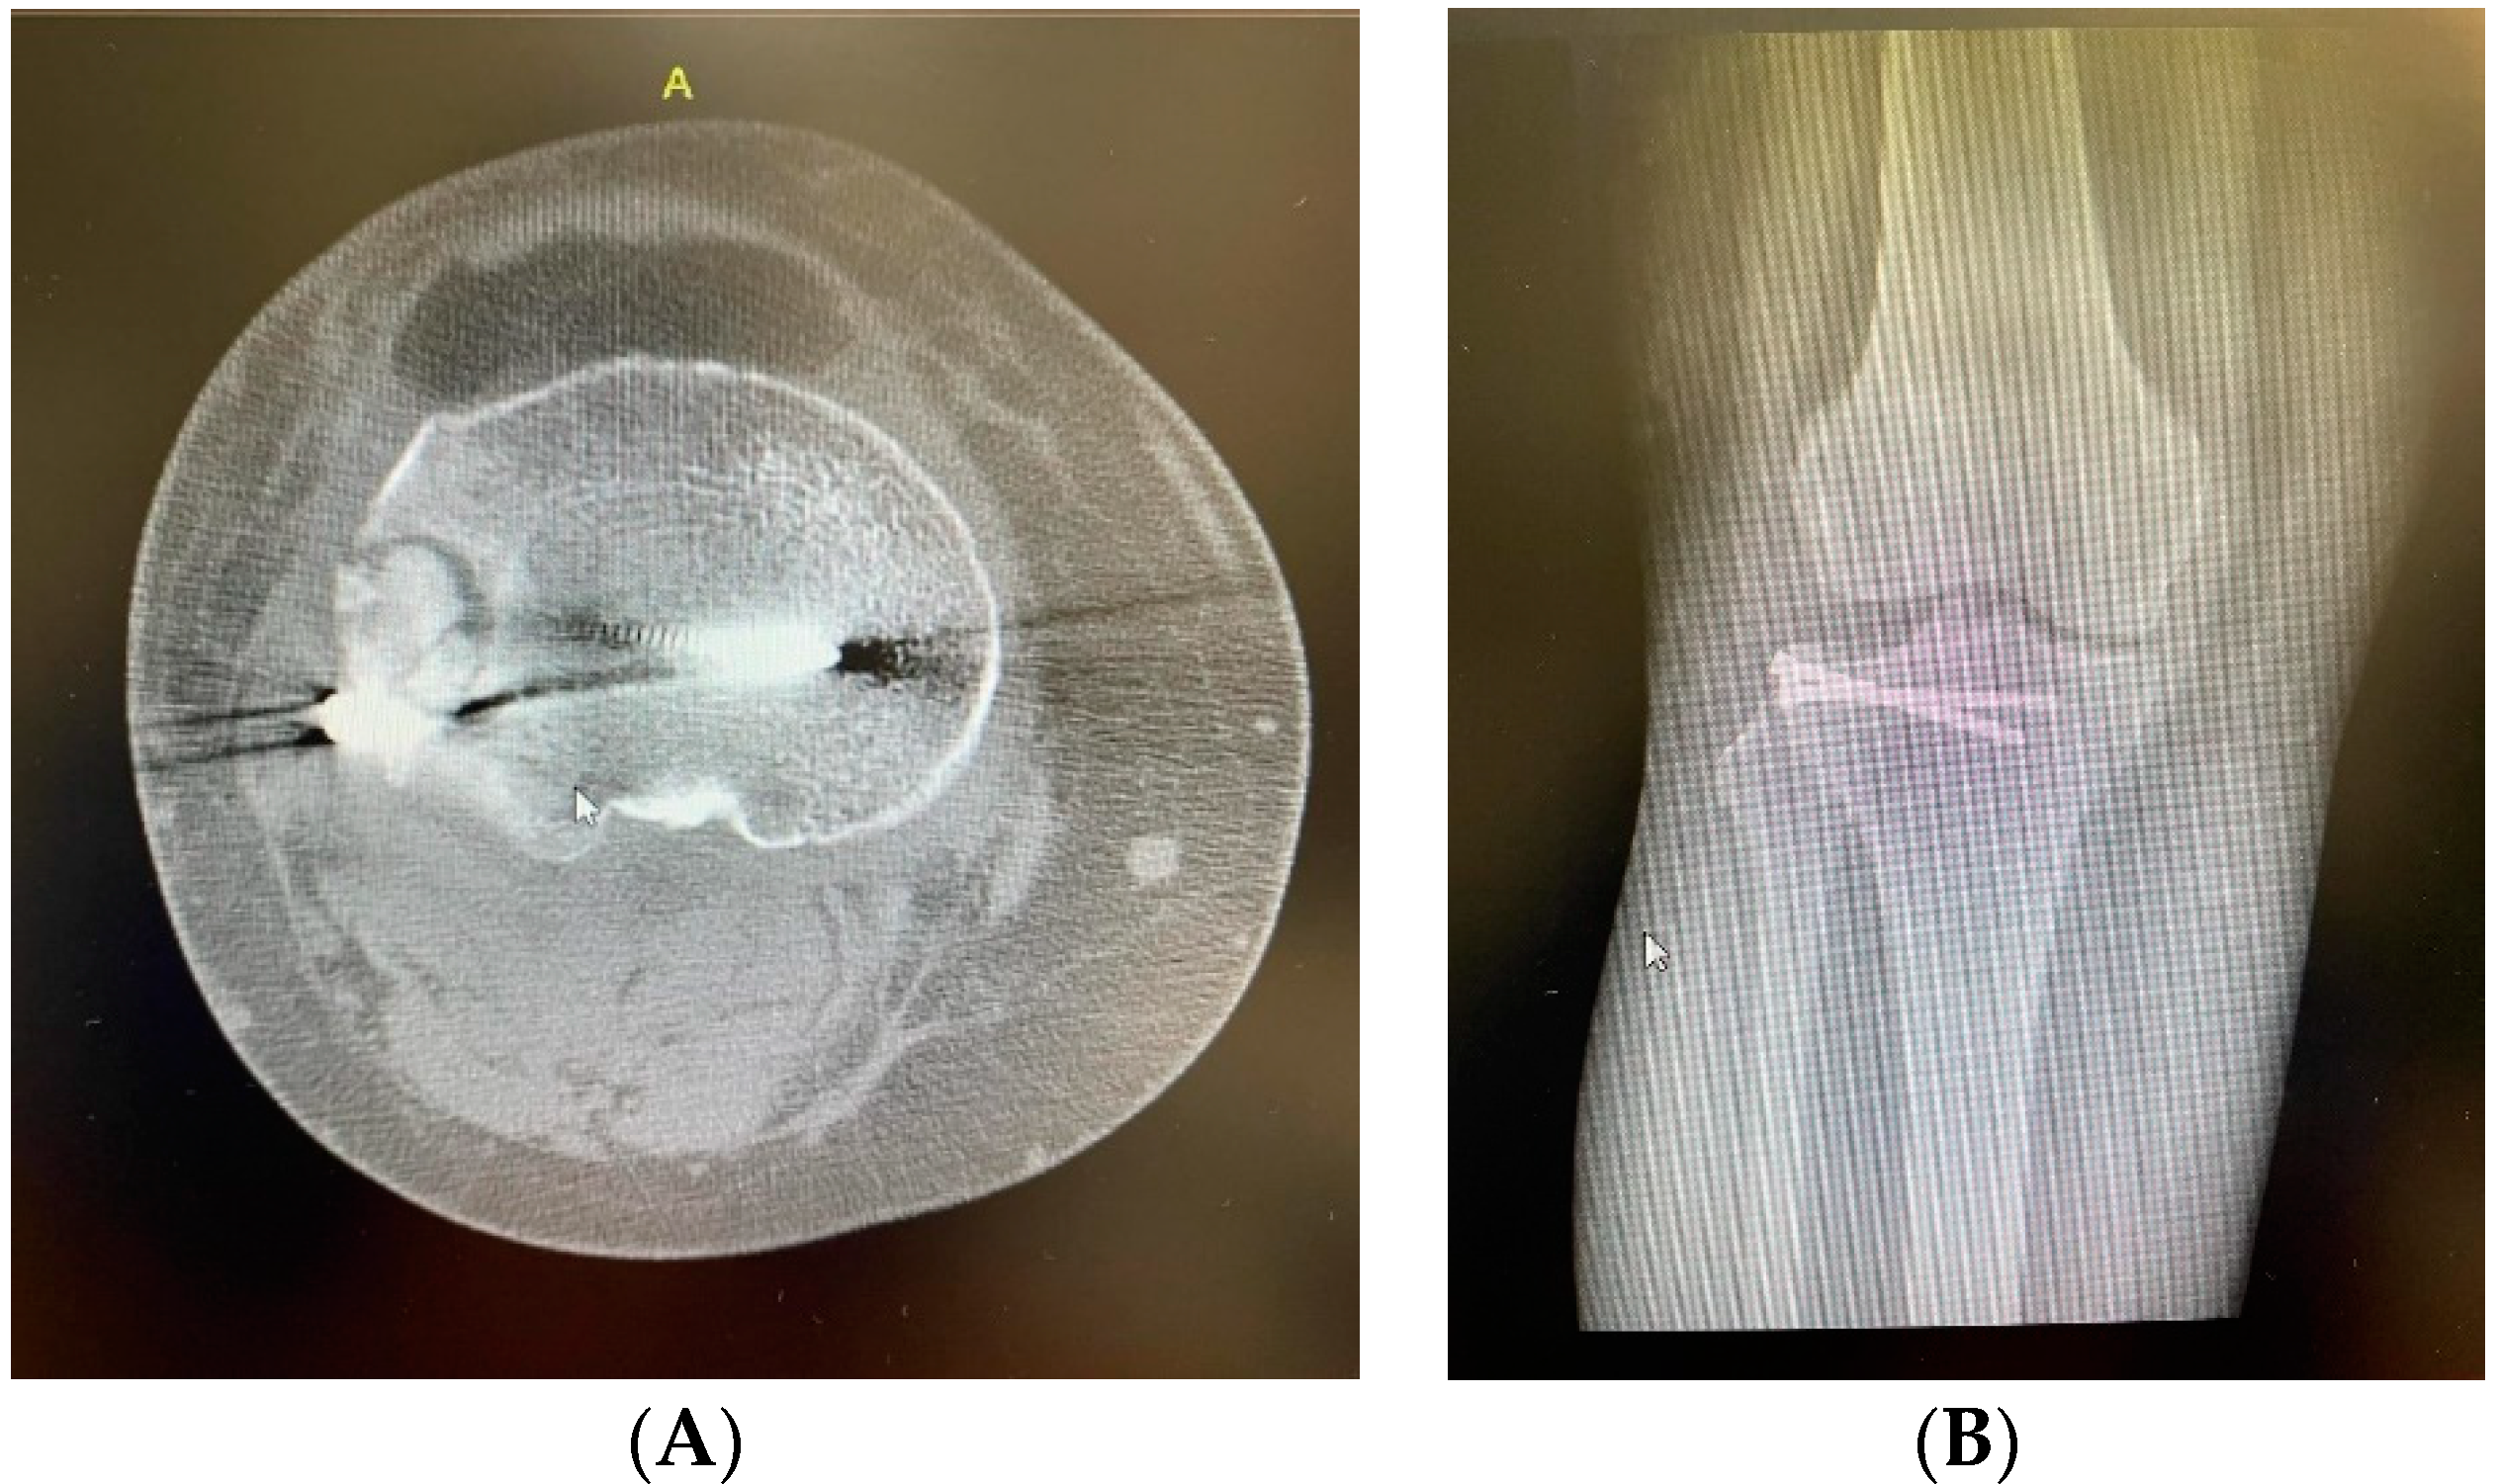

2. Clinical Case Presentation